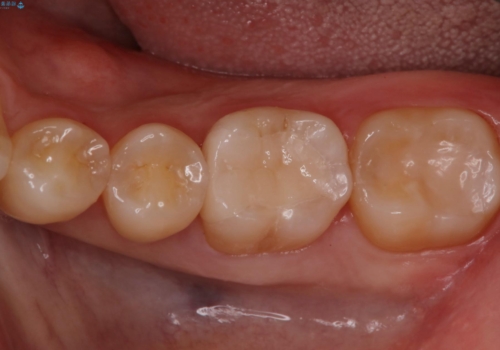

海外に引っ越す予定があり、見ため(審美性)強度ともに良い被せ物を希望されたため、セラミックインレーにて治療を行いました。

一部歯に保険治療で使用されている材料が劣化していたため、う蝕と一緒に取り除いて劣化の少ないセラミックに置き換わりました。